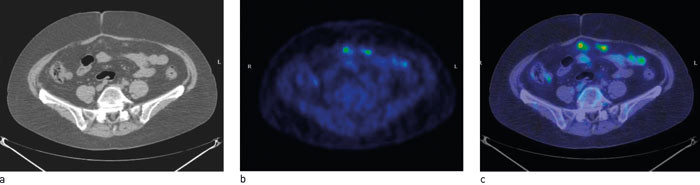

En positronemitterende substans som gir tilsvarende bildeinformasjon som MIBG-scintigrafi, men bedre oppløsning er 11C-hydroksyefedrin (11C-HED) (18, 19). Metoden kan brukes ved mistanke om tumorer fra det sympatiske nervesystemet (feokromocytom, paragangliom, nevroblastom). Det anbefales å seponere en rekke farmaka før undersøkelsen. Opptak er fysiologisk i lever og i alle organer med sympatisk innervasjon (spyttkjertler, hjerte), og stoffet utskilles via nyrene. Fokalt opptak utenfor disse organene er tumorsuspekt, med en sensitivitet på 90 % og en spesifisitet på nesten 100 % (19). Fokalt opptak i en binyre etablerer diagnosen feokromocytom (fig 2). I en studie med 11C-HED-PET hos 12 pasienter med 13 feokromocytomer viste metoden 92 % sensitivitet og 100 % spesifisitet (19).